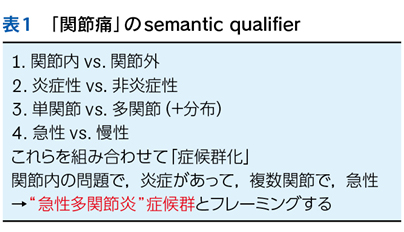

4 semantic qualifier(SQ)

▶ 「yieldの高いプロブレムを同定し問題の中心に据える」以外に問題のyieldを高める方法として,プロブレムを医学的用語で「修飾(qualify)」することがある。「発熱」というプロブレムはlow yield(二等星)だが,修飾を加えて「左下腹痛を伴う急性発熱」や「CRP陰性の遷延性発熱」という問題となればかなりyieldは上がる。このように,中心に据えたプロブレムがlow yieldでも,修飾することでhigh yieldとなり,「適切な問題」となりうる(図5)。この際に利用する医学的修飾語句をsemantic qualifier(SQ)と呼ぶ。

▶ semanticは直訳すれば「意味の」となるが,semantic qualifierを診断推論の文脈で訳すなら,「意味を限定する修飾語句」とでもなるだろう。先述のように,フレーミングに用いる問題を定義するにあたっては,個別具体的な情報は捨象され,抽象化・一般化された概念となっている必要がある。ゆえにSQも抽象的・一般的な医学用語に「翻訳」して表現する(表1)。